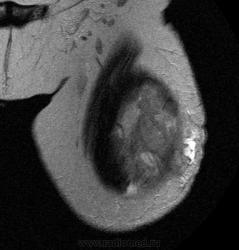

Пациентке 79 лет, с жалобами на болезненность и наростающую припухлость по передне-латеральной поверхности левого бедра в течении 3х месяцев, было проведено исследование в октябре по поводу объемного образования мягких тканей левого бедра.

Т2/ВИ

В толще проекции латеральной головки четырехглавой мышцы визуализируется объемное образование неоднородной с визуализируемой псевдокапсулой, интимно прилежит к бедренной кости, без признаков нарушения целостности кортекса, костный мозг интактен. В наружных отделах прерывание капсулы с выходом на поверхность кожных покровов. Неравномерно контрастируется. Похожа на рабдомиосаркому.

Гистология: фибро-саркома. После первого исследования пациентка была прооперирована и ей была проведена химиотерапия совместно с лучевой. Второе исследование проведено в конце ноября. Ваше мнение?